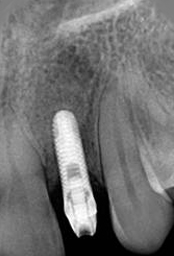

X-ray of Implant + Abutment

Single Tooth Implant